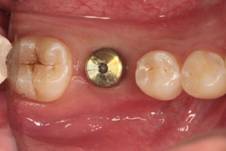

种植治疗是一种以植入骨组织内的下部结构(种植体)为基础来支持/固位上部修复体的缺失牙修复方式,是治疗牙齿缺失的一种较新的、成熟的临床技术。医生需要根据理想的缺失牙修复方案所要求的植体分布和三维方向、结合患者口腔局部和全身条件,设计制定合理的种植外科方案后,经手术方法将种植体植入组织内(通常是上下颌)、并获得骨组织牢固的固位支持,最后通过特殊的装置和方式连接支持上部的修复体。目前常用的种植体材料主要是钛、上部暴露于口腔内的修复体材料趋同于天然牙修复材料。

修复导向种植治疗方法的主要优点是主要依靠种植体的支持,恢复缺牙区的软硬组织形态、实现预期的功能与美学目标,这种方式更加符合口腔生物力学的要求,从而有利于获得更为长期的修复成功率。

(图片由修复科韩彦峰医生提供)